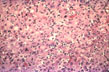

Fig. 134 - Infectious mononucleosis heapatitis

High power of previous illustration showing the signs of high regenerative activity: binucleate cells and a mitotic figure. H&E stain.